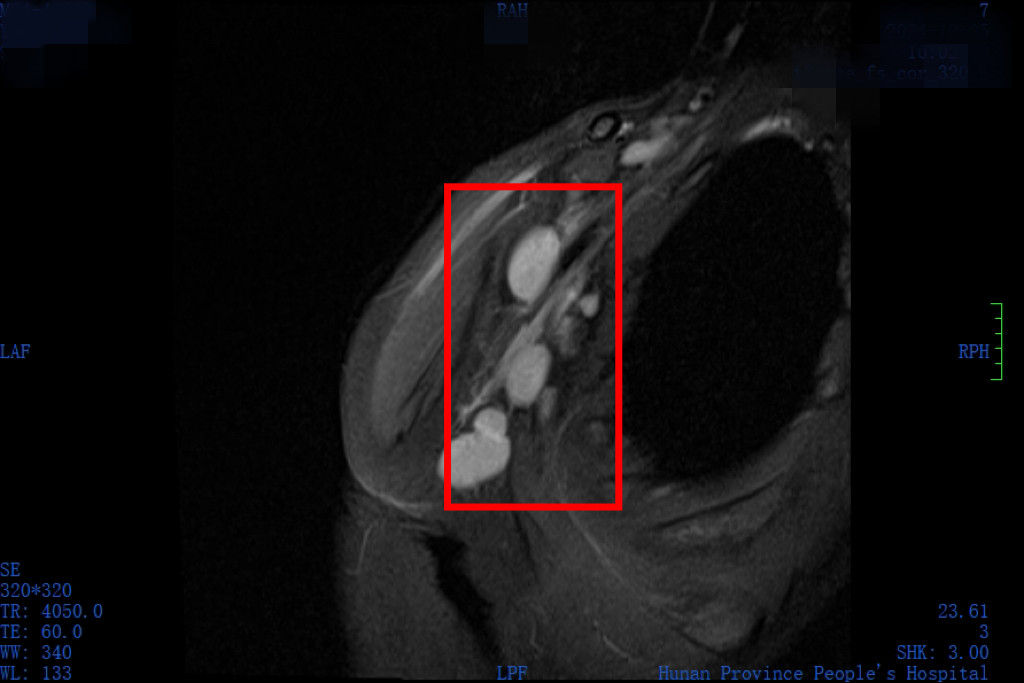

经磁共振检查,小乐左腋窝和锁骨上窝有多发的肿大淋巴结,内部已经出现凝固性坏死,增强扫描以边缘环形强化为主,符合特殊病原体上行感染所致。循着这一线索,医生为小乐进行了淋巴结穿刺活检及穿刺物宏基因检测,结果证实感染了汉赛巴尔通体感染,正是“猫抓病”。经过几天的抗感染及对症治疗,小乐病情好转,10月11日出院。